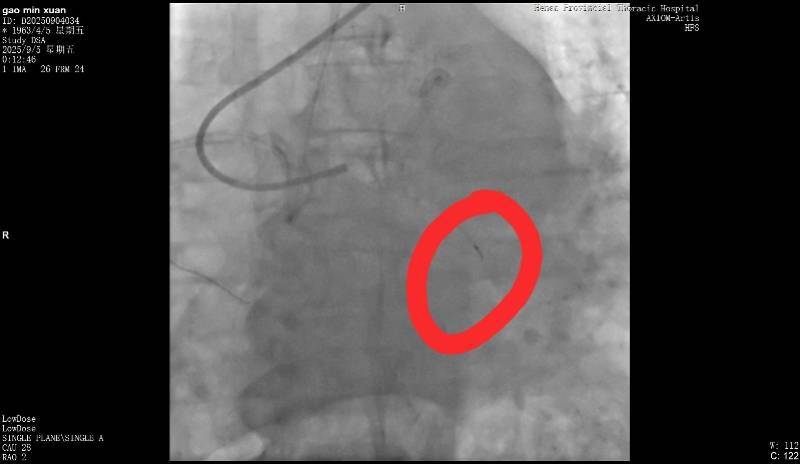

断裂的导丝皇冠信用网在线注册。受访者供图

9月5日,高女士父亲在该医院做冠脉造影,手术进行了近3个小时皇冠信用网在线注册。高女士回忆说,手术结束后,负责手术的医生告诉她,“在微创探查体内的时候,一截导丝断裂。”当高女士询问能否再次实施手术取出时,医生表示因病患年纪较大,开胸手术存在危险,并没有取出的必要。但对于遗留导丝会否在后续造成长期影响,该医生则称“无法确定”。

高女士提供的病程记录显示,“手术操作过程中出现回撤导丝困难,送入微导管尝试至坎顿处未成功,退出微导管时远段导丝断裂,多途径尝试取出断裂导丝均未能成功皇冠信用网在线注册。”资料还指出,“通过复查造影,回旋支近段残余狭窄小于30%,未见明显夹层、无复流。”

南都记者留意到,该病程记录给出了心血管外科一病区会诊意见,称“回旋支内见离断的介入导丝,外科取出导丝意义不大,建议内科治疗”皇冠信用网在线注册。